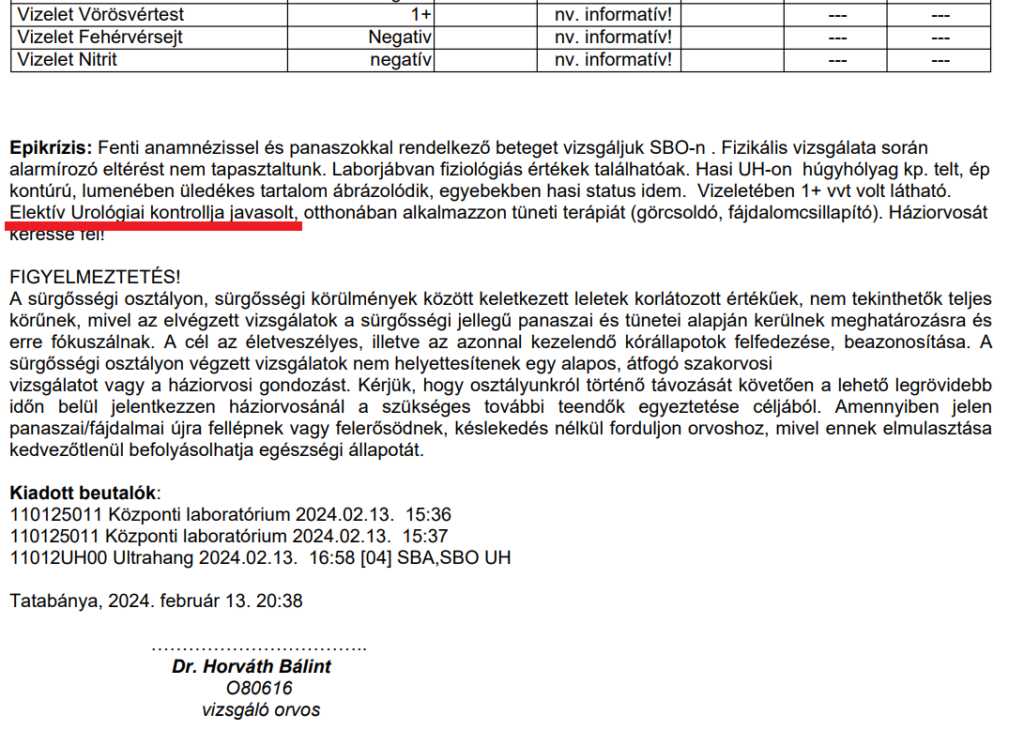

Készült egy hasi ultrahang. Ezután egy rezidens azt mondta a fiamnak: „Nos, Zsolt, megnéztem a papírjait, mondja meg, hogy mit szeretne tőlünk?”. Ez elképesztő! Fiamat kisebb sokként érte, azt hitte egy kórházban van, orvosokkal, azért jött, hogy megadják a segítséget. Ekkora vérvizelés, fájdalom, objektív leletek mellett a beteg mondja meg, hogy mit csináljanak vele? Nem volt a sürgősségin egy urológus, nefrológus szakorvos, de még csak egy belgyógyászt sem hívtak le hozzá! Nem érezték úgy, hogy a felső határérték 1000-szeres vérvizelési értékével és egyéb paraméterekkel, illetve súlyos állapotában azonnal osztályos felvétel és intravénás kezelés kell? Megjegyzés: Dr Horváth Bálint a fiamat nem vizsgálta, így a „vizsgáló orvos” az ambuláns lap alján hazugság, és Dr Horváth Bálint szintén nem rögzítette, hogy 5 nappal korábban 500-szoros és 1000-szeres húgyúti vérzése volt Zsoltnak, egyéb más pozitív paraméter mellett. (Gondoljuk direkt nem írta le, hiszen akkor nincs mód elektívezni, akkor azonnali betegfelvétel van.), A fájdalmairól, a napi vizeletek számáról nem is beszélve, ami meghaladta a 18-20-at, hasmenése pedig napi 5-8-at, egy összeomló akut állapot volt már ekkor! Nem elektív, úristen, hová kerültünk!!!

Dr Horváth Bálint általános orvos elektivezgetik. És ellátás nélkül elküldi a fiamat! Találkoztunk vele többször is, mármint úgy, hogy mint elment a fiam mellett. Zsolt szerint, aki látta viselkedését, ilyen embereknek tilos lenne dolgozni sürgősségi osztályokon. Nem tudtuk, hogyan tovább, becsomagolva jöttünk ide is és mi lett belőle?